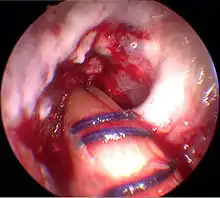

Arthroscopie diagnostique

La sécurité diagnostique la meilleure est obtenue par arthroscopie diagnostique. Ce procédé représente l'étalon-or pour le diagnostic de la rupture de LC. Ce procédé relève d'une chirurgie invasive au minimum, mais comporte certains risques, comme toute intervention chirurgicale dans le genou du patient[113]. Comme cependant le traitement chirurgical d'une rupture de LC sera conduit par chirurgie arthroscopique, il est possible d'enchaîner celle-ci immédiatement après l'arthroscopie diagnostique, par la résection partielle du ligament (pour une déchirure) ou la reconstruction en cas d'arrachement. Avec l'accroissement de la facilité de l'IRM, le nombre d'arthroscopies purement diagnostiques a nettement diminué ces dernières années[114],[115]. L'arthroscopie diagnostique est quand même utilisée comme précédemment comme procédé de choix pour une compréhension certaine du diagnostic de rupture de LC, en cas d'examen clinique confus et d'IRM difficile à interpréter[113].

Arthroscopie

L'opération proprement dite commence par l'introduction de l'arthroscope dans le genou du patient. Ceci permet de confirmer définitivement le diagnostic de rupture de LC. Les autres blessures, en particulier celles des ménisques, peuvent être soignées avant la reconstruction du LC.